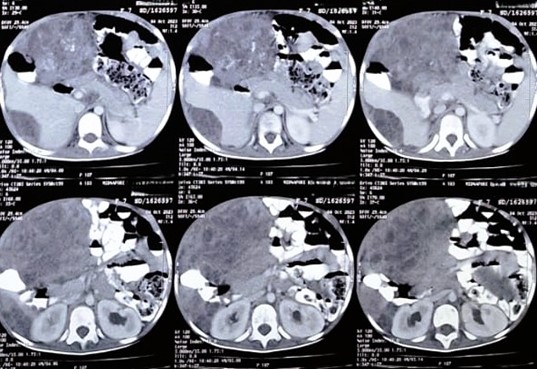

Figure 4: CECT whole abdomen (axial view), Postoperative (after few months of defaulter) showing huge intraabdominal SOL almost occupying whole abdomen.

Then she again presented with huge abdominal distension and was unable to walk. She was again evaluated for the disease status. The Blood parameters, as on 01/08/2023, were: BetaHCG -> 96120 mIU/ml, CA-125 –> 207.5 U/ml, Sr LDH -> 4180 U/L, AFP –> more than 1000 ng/ml. CECT scan Thorax and Abdomen on 07.08.2023 showed, Large heterogenous enhancing SOL of 8.1 x 6.3 x 6.1 CM in POD, invading and incaving the ano-rectum region with bilateral pleural effusion.